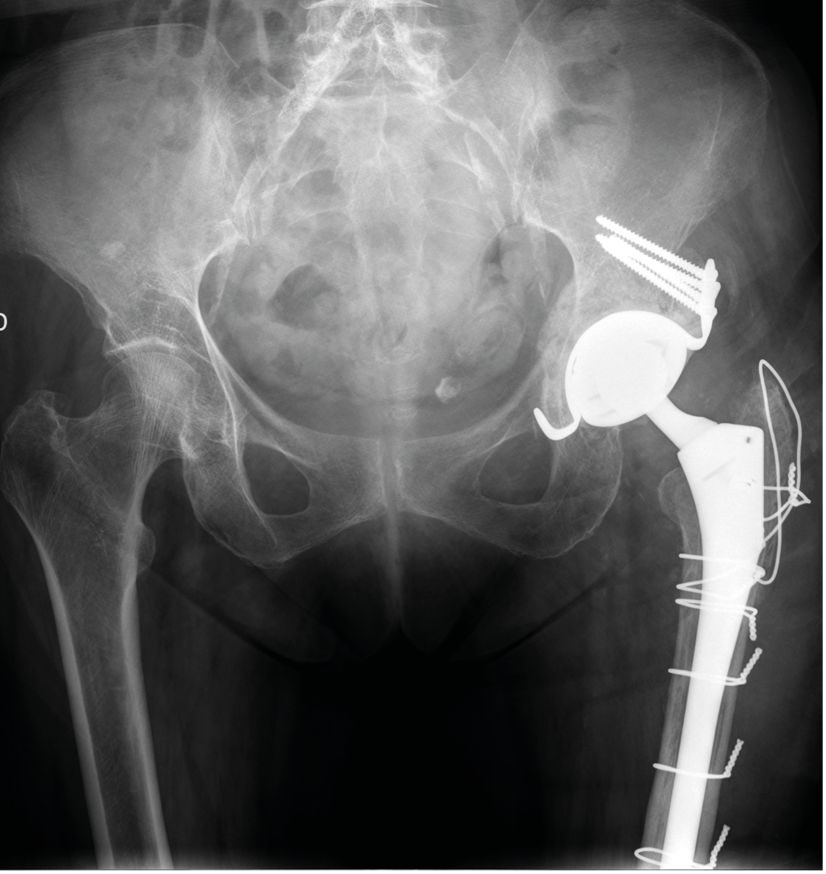

Case report n° 7

82-year-old female Fractured neck of femur while cross-country skiing

- Hemiarthroplasty

- 3 early dislocations

- Single component revision R1 conversion to dual mobility THA

- 2 further episodes of dislocation reduced under GA

- Feels like hip is clicking ever since last dislocation

Two component revision (R2) (Figures 11 & 12)

Infection on D15:

- Debridement, moving parts changed, antibiotics

- Radiography after 1 year

- Walking unrestricted with a stick (has stopped cross-country skiing)